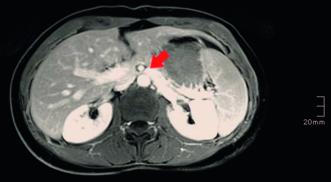

In unserer Anamnese der seit vielen Jahren bestehenden Unterbauchschmerzen zeigten sich lageabhängige Beschwerden, die im Tagesverlauf zunahmen und in die Leistengegend sowie den Oberschenkel ausstrahlten. Ergänzt wurde die Anamnese durch Feststellung einer Pollakisurie und Dyspareunie. In der angiologischen Diagnostik konnte mittels farbkodierter Duplexsonographie eine Nutcracker-Anatomie (Einklemmung der linken Nierenvene zwischen der oberen Darmarterie und der Bauchaorta) und eine May-Thurner-Anatomie (Kompression der linken Vena iliaca commuis durch die rechte Arteria iliaca communis) festgestellt werden (Abb. 4, 5). In der MR-Phlebographie fanden wir ausgeprägte parauterine Varizen und eine stark erweiterte insuffiziente Vena ovarica links (Abb. 6).